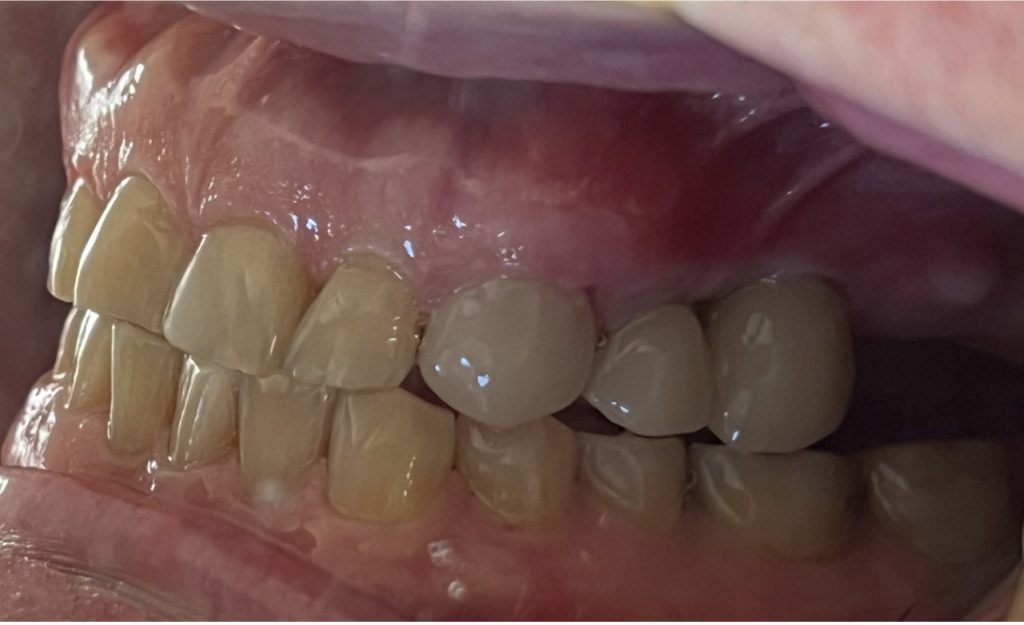

The aim is to improve your health, chewing function and/or aesthetic appearance and once healing and restoration is complete you will be able to enjoy a wide variety of foods again.

- A single tooth is missing – Crowns